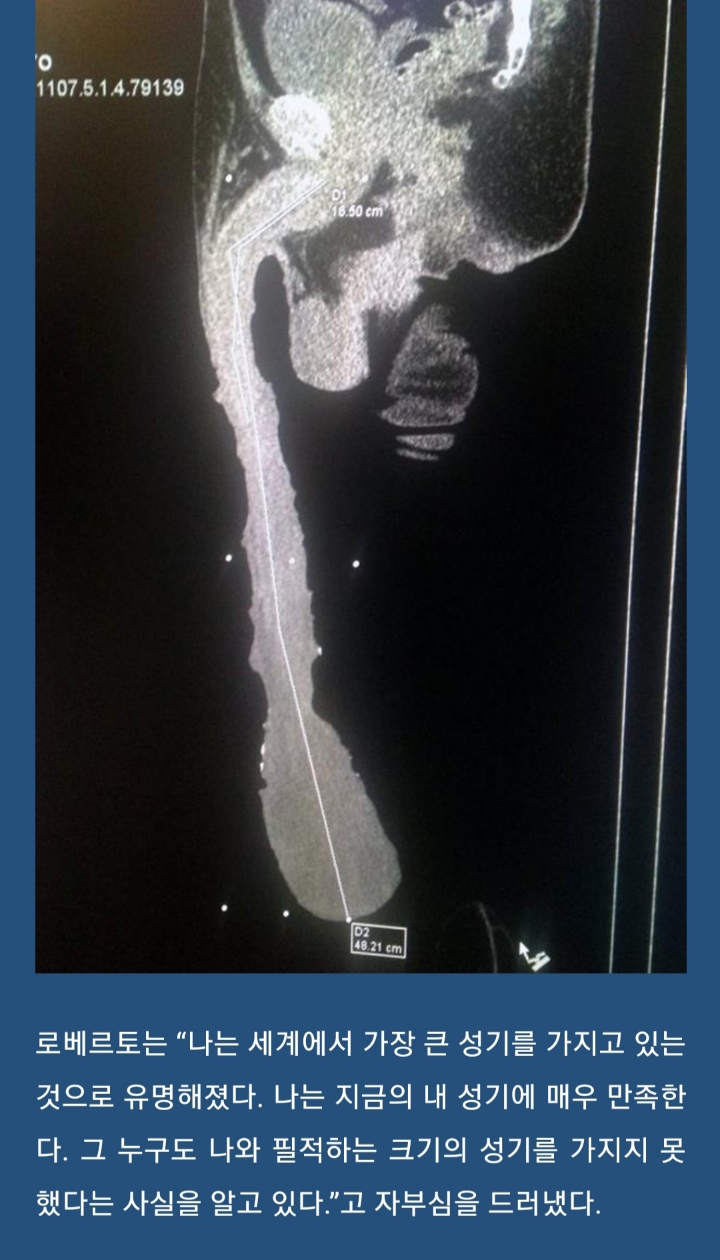

세계에서 가장 긴 페니스를 가진 남자

기네스가 인정 안하는 이유

대부분의 길이가 걍 껍질(포피. 포경할때 자르는 그 부분)

알맹이는 17cm 미만(요도선이 방광에서 출구까지인거루감안하면 페니스길이는 10cm 내외...)